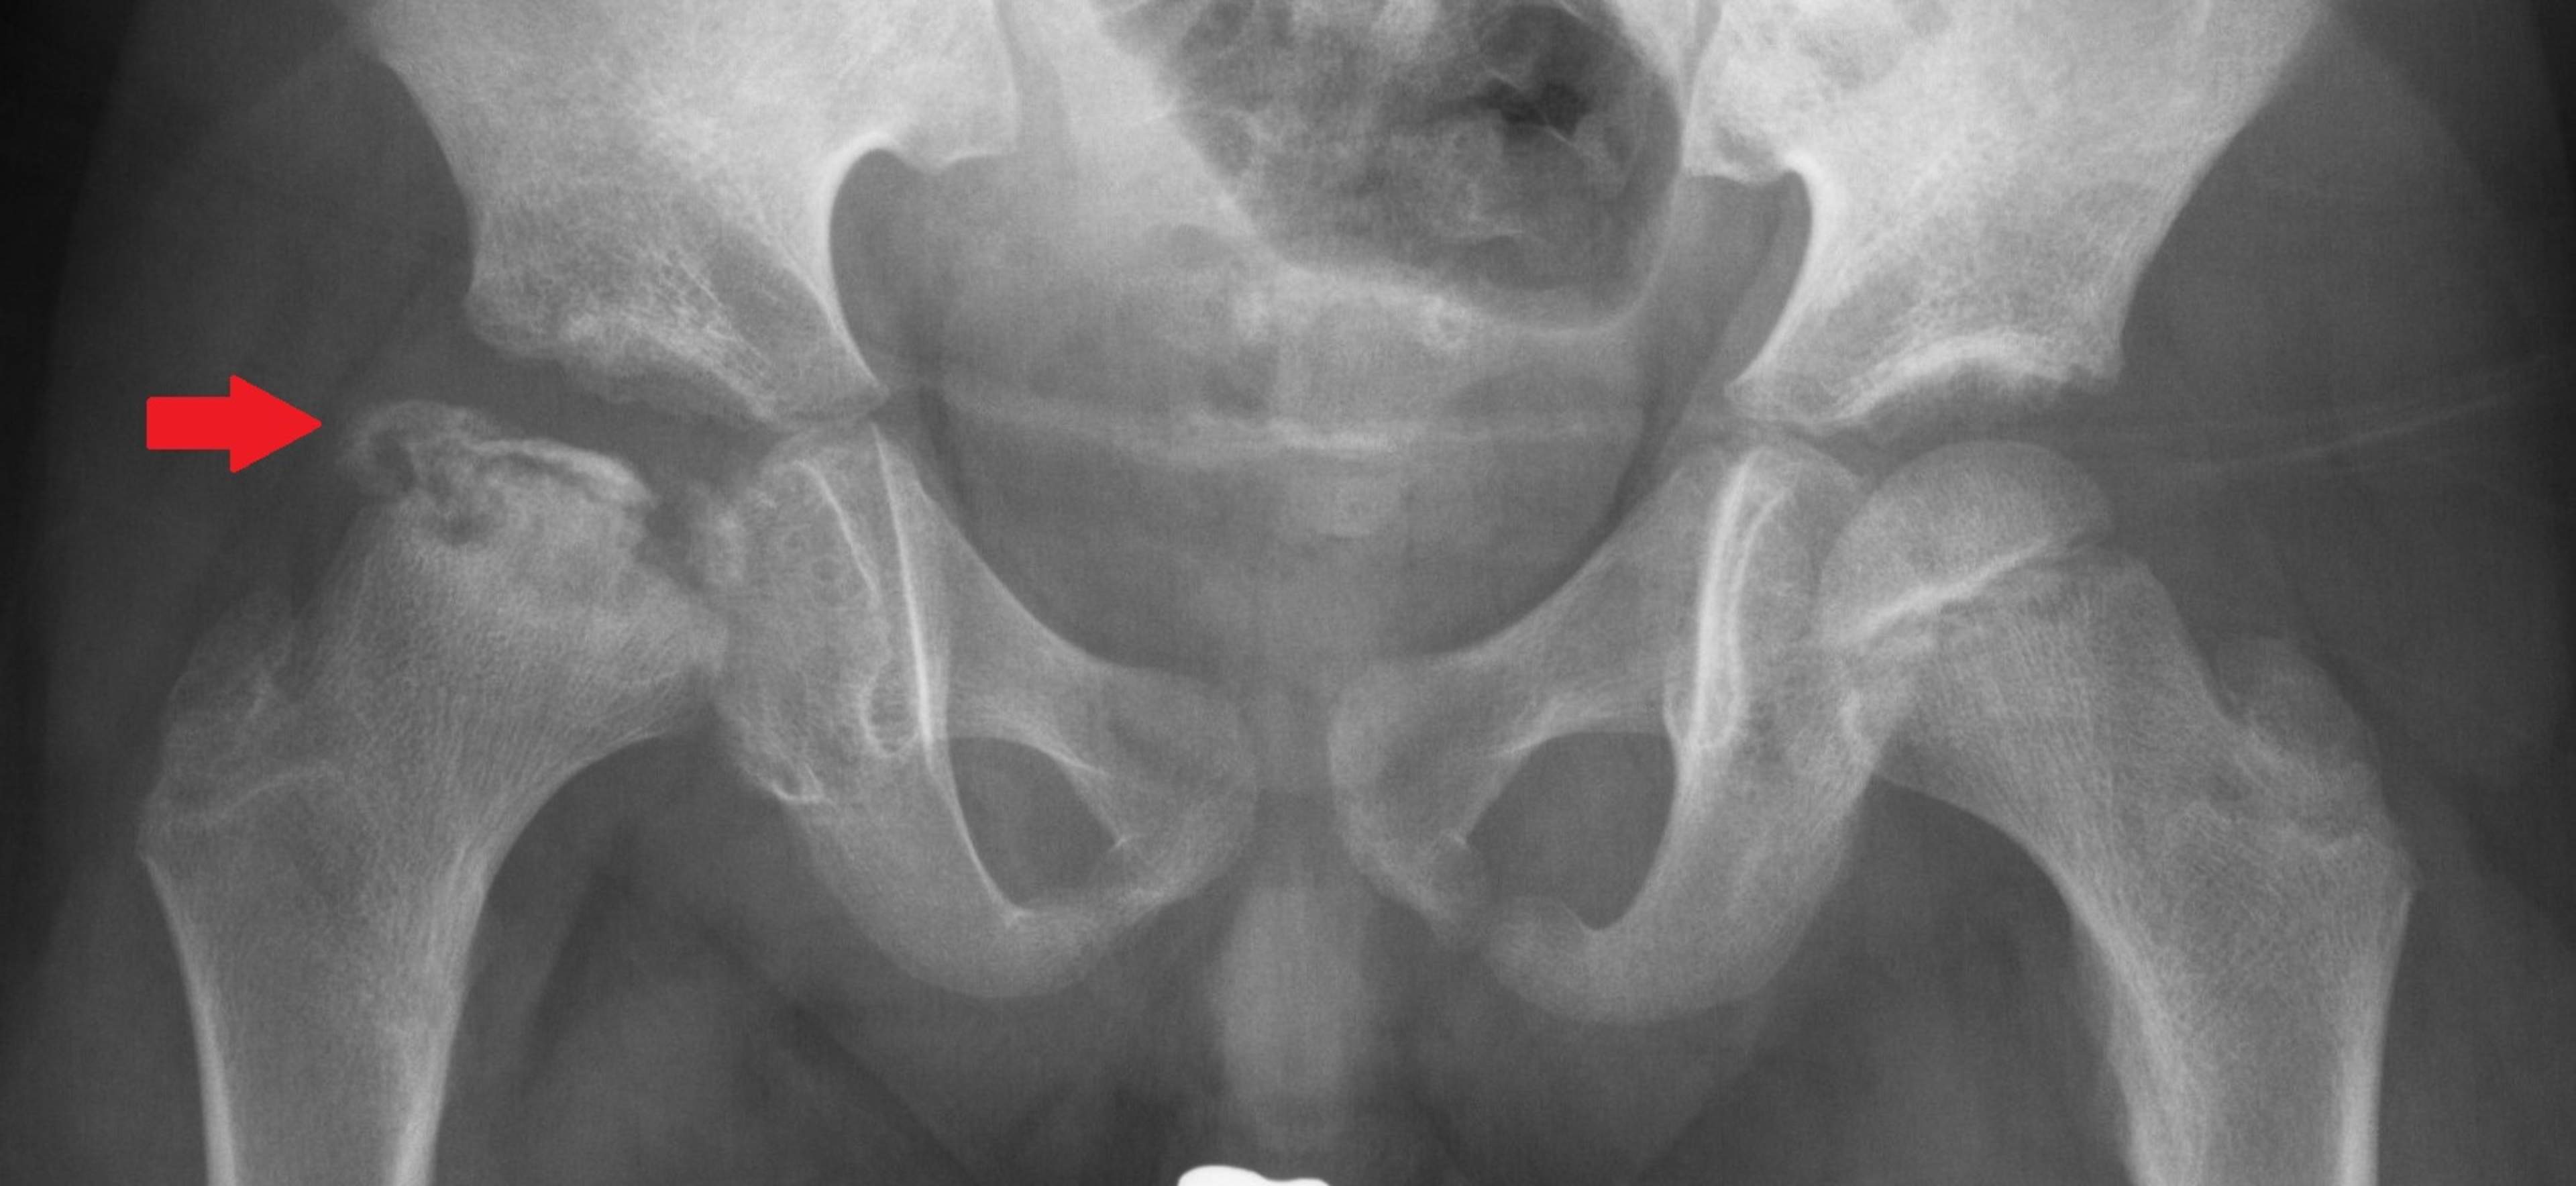

Legg-Calvé-Perthesin tauti johtuu reisiluun pään verenkiertohäiriöstä, jonka syy on tuntematon. Verenkiertohäiriön seurauksena reisiluun pään luutumistumake menee osittain kuolioon, jonka vuoksi reisiluun pään muoto muuttuu ja lonkkaan kehittyy liikerajoitusta ja kipua. Tautia esiintyy leikki- ja kouluikäisillä lapsilla, pojilla enemmän kuin tytöillä. Paranemisprosessi voi kestää useita vuosia. Taudin ennuste on yleensä hyvä, mikäli se alkaa ennen esikouluikää. Vaikeimmillaan tauti voi johtaa lonkan liikerajoitukseen, alaraajojen pituuseroon ja ennenaikaiseen nivelrikkoon aikuisiällä.